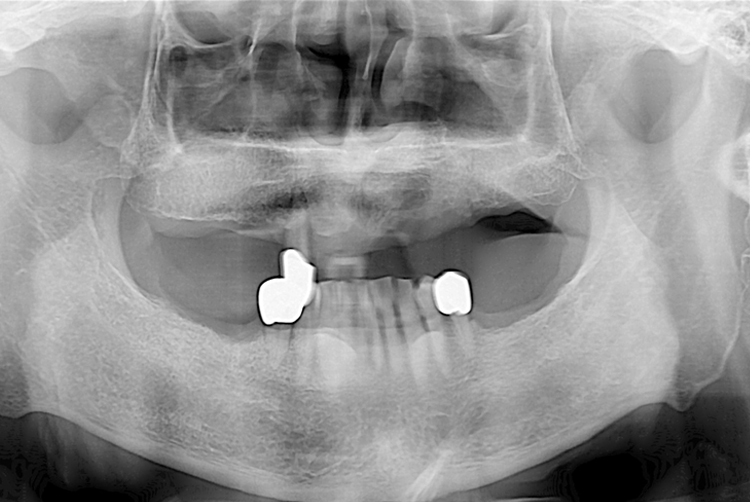

[임플란트] 임플란트

치료전 : 2019-07-18

세종치과는 많은 환자와 다양한 케이스를 바탕으로 항상 편안한 임플란트 수술을 제공하고자 노력하고,

오래동안 튼튼히 쓸 수 있는 임플란트 수술을 가장 큰 목표로 삼고 있습니다